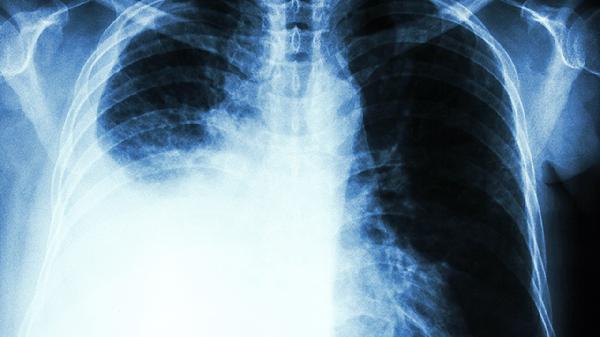

肺癌晚期发生骨转移怎么办

肺癌晚期发生骨转移可通过镇痛治疗、靶向治疗、放射治疗、双膦酸盐治疗、手术治疗等方式缓解症状。骨转移通常由肿瘤细胞通过血液或淋巴系统扩散至骨骼引起,可能伴随病理性骨折、持续性骨痛、高钙血症等症状。